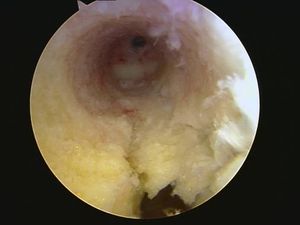

| Visión artroscópica de una rotura reciente y sangrante del Ligamento Cruzado Anterior (LCA). | |

| Visión artroscópica de una rotura reciente del Ligamento Cruzado Anterior. Véase la importancia de la palpación para la valoración de la competencia del LCA. | |

| Ausencia del LCA junto con una rotura en asa de cubo de menisco interno que se encuentra alojada en la escotadura femoral. | |